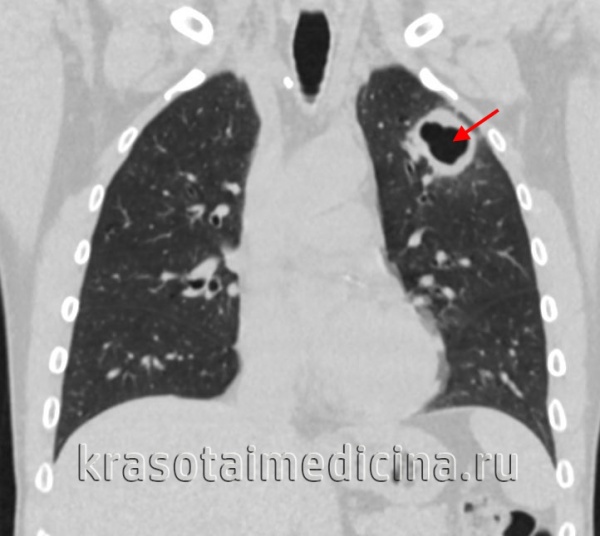

Первичный туберкулезный комплекс

Данная форма туберкулеза у детей характеризуется триадой признаков: развитием специфической реакции воспаления в очаге внедрения инфекции, лимфангитом и поражением региональных лимфоузлов. Развивается при сочетании массивности и высокой вирулентности туберкулезной инфекции со снижением иммунобиологических свойств организма. Первичный туберкулезный комплекс может локализоваться в легочной ткани (95%), кишечнике, реже – в коже, миндалинах, слизистой оболочке носа, в среднем ухе.

Заболевание может начинаться остро или подостро; маскироваться под грипп, острую пневмонию, плеврит либо протекать бессимптомно. Клинические проявления включают интоксикационный синдром, субфебрилитет, кашель, одышку. Изменения в первичном очаге проходят инфильтративную фазу, фазу рассасывания, уплотнения и кальцинации (формирования очага Гона).